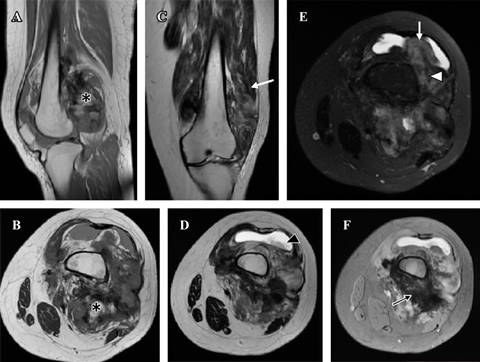

Magnetic Resonance showed a heterogeneous tumor, with large areas of low signal strength in all the sequences, alternating with areas of fat behavior) and zones of intermediate intensity (Figure 3).

Figure 3: Magnetic Resonance. (A y B) T1 sagittal and axial, (C y D) T2 coronal and axial, (E) T2 with coronal fat saturation, (F) Gradient echo in axial plane. Heterogeneous tumor, with large areas of low signal strength in all the sequences, in relation to tumor ossification (black arrow), alternating with areas of greasy behavior (*) intermediate intensity zones (white arrowhead), infiltrating both vastus muscles, mainly the lateral and suprapatellar recesses (white arrow), conditioning joint effusion (black arrowhead).